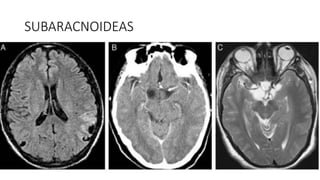

SUBARACNOIDEAS

• #40 Cisticercos subaracnoideos. Estudio de RM mediante secuencia FLAIR en el plano transversal (A), en la que se observan peque˜nos quistes en la profundidad de los surcos cerebrales biparietales. Lesiones quísticas en las cisternas basales. La TC con contraste (B) y la secuencia de RM potenciada en T2 (C), ambas en el plano transversal, muestran la ocupación de las cisternas basales por lesiones quísticas cuyo contenido es similar al líquido cefalorraquídeo.